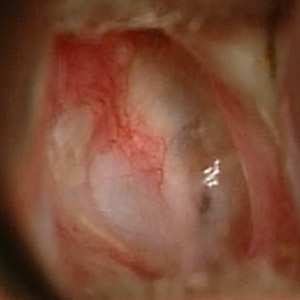

Trommelfell nach Rekonstruktion Knorpelhaut

Trommelfell nach Rekonstruktion Knorpel und Perichondrium